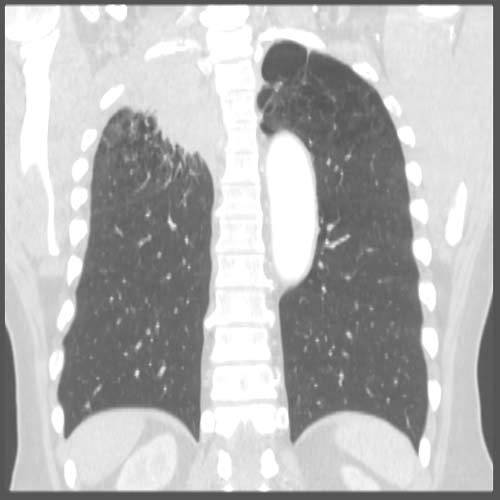

Bronchioalveolar subtype (carcinoma in situ): CXR often shows hazy infiltrates similar to pneumonia; excellent prognosis

The bronchioalveolay subtype grows along alveolar septa–> apparent thickening of alveolar walls